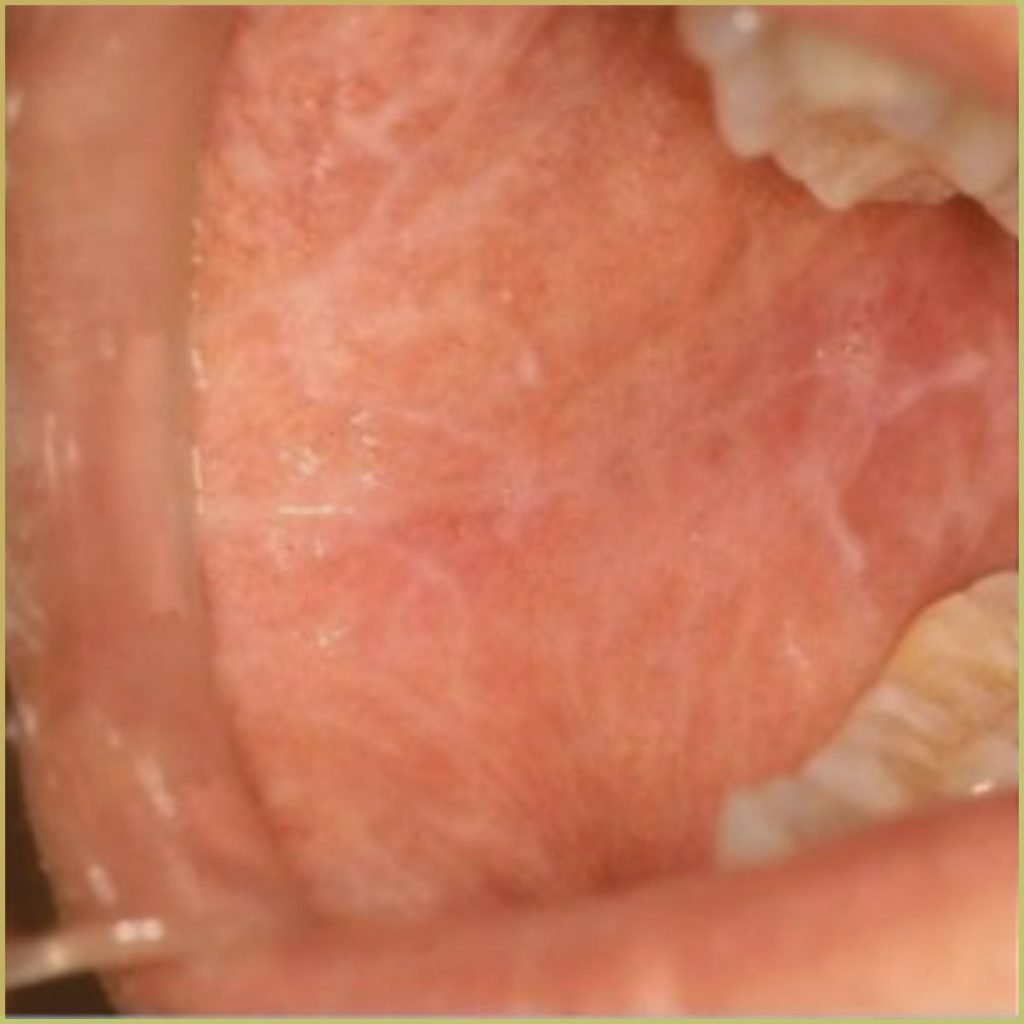

GEOGRAPHIC TONGUE

Geographic tongue (migratory glossitis, erythema migrans) is a distinct condition appearing as a map-like pattern on the dorsum of the patient’s tongue. It is caused by the loss of dorsal papillae, but the reason for depapillation is not well understood. The common clinical presentation includes:

- Focal red depapillated areas bordered by yellowish margins.

- Areas of depapillation may migrate over time.

- Can be associated with fissured (scrotal) tongue.

- Primarily affects the dorsum (top) and lateral borders of the tongue, but can occasionally appear on other mucosal sites, such as the floor of the mouth and cheek mucosa.

- Some individuals may experience mild discomfort or a burning sensation, particularly when consuming spicy, acidic, or hot foods.

- Many cases are asymptomatic, with individuals only becoming aware of the condition during routine dental or medical examinations.

Diagnosis is usually based on the lesion history and clinical presentation alone. Your differential diagnosis should include:

- Lichen planus.

- Lupus erythematosus.

- Candidiasis.

- Psoriasis.

The condition is benign and self-limiting. Topical corticosteroids may be appropriate if the lesion is symptomatic.